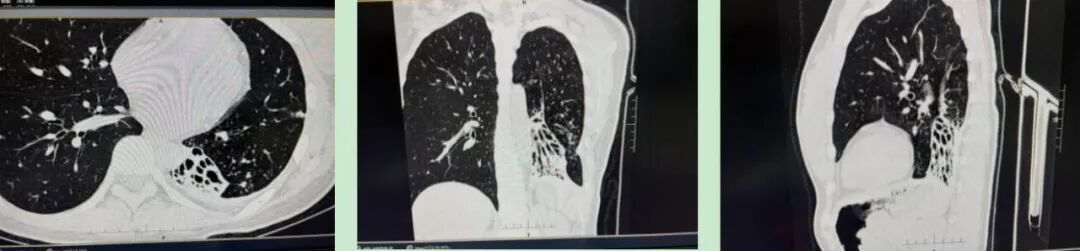

7 个月前,20多岁的小林突发咳嗽、咳痰,在其他医院治疗后病情未得到控制,还出现痰中带血、呼吸困难的症状,遂至中信惠州医院呼吸医学中心就诊。胸部 HRCT 检查显示:1.双肺多叶段多形态感染性病变,请结合临床实验室检查除外继发性肺结核,真菌感染等。2.左肺下叶实变、体积缩小,肺不张。3.左肺门及纵隔淋巴结钙化。纵隔向左侧偏移。4.左侧胸膜肥厚并钙化。

手术前影像图像